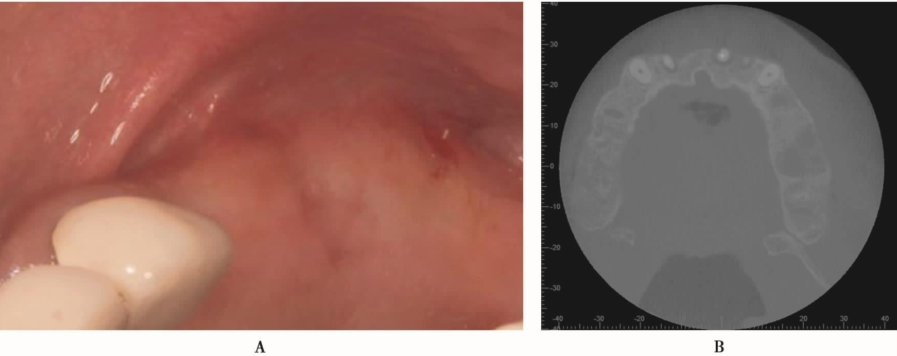

Stephen S.报道,使用机械磨头开窗,黏骨膜的穿孔率平均为30%,绝大多数穿孔发生在使用机械磨头和使用剥离器械进入上颌窦的时候,而不是在剥离的过程;而使用超声骨刀开窗:黏骨膜的穿孔率为7%。下面是一例上颌窦外提升手术过程中上颌窦黏膜发生穿通的病例。患者,女性,37岁,全身状况良好,要求种植牙修复。B5缺失,缺牙间隙大小合适,牙槽骨宽度理想(图11)。

图11 B5缺失,口内观A.颊面观;B.𬌗面观

术前CBCT显示缺牙区牙槽嵴顶到上颌窦底的最小高度约3mm,上颌窦底黏膜约1mm,上颌窦腔影像清澈,无炎症,侧壁厚度1~2mm(图12)。

图12 术前CBCTA.冠状面;B.矢状面